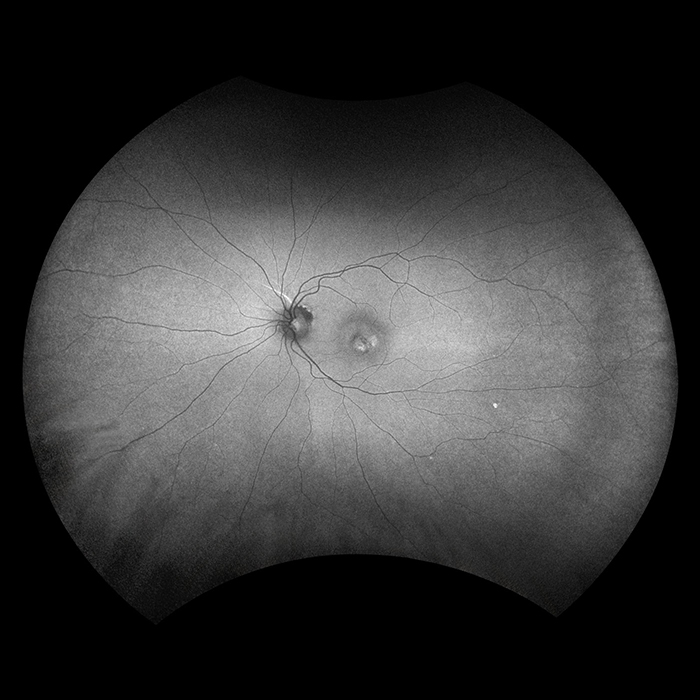

Optos introduced ultra-widefield (UWF™) retinal imaging to enable eyecare professionals to discover, diagnose, document and treat ocular pathology that may first present in the periphery - pathology which may go undetected using traditional examination techniques and equipment. Our UWF, high-resolution retinal imaging devices each image more than 80% or 200˚ of the retina in a single shot. Our complete list of ultra-widefield retinal imaging devices is below.

Silverstone RGB is redefining excellence in retinal imaging. It is the only device that captures true color, 200° optomap ultra-widefield images in a single shot, seamlessly integrated with guided swept-source OCT. For the first time, eye care professionals can access nine powerful imaging modalities in one system, each designed to image pathology anywhere in the retina.

optomap has been shown to enhance pathology detection, disease management, and to improve clinic flow. Now with nine retinal imaging modalities, including integrated, peripheral Swept Source OCT, Silverstone RGB facilitates examination of the retina from vitreous through the choroidal-scleral interface.

California was developed for medical imaging and is a standard for retinal screening programs. California is available in multiple models with multiple imaging modality options. California produces a 200°, single shot retinal image of unrivaled clarity in less than ½ second and is changing the management of diseases including Geographic Atrophy, Diabetic Retinopathy, AMD, and Uveitis.

Daytona produces a 200° single shot optomap retinal image of unrivaled clarity in less than ½ second. This fast, easy, patient-friendly, ultra-widefield imaging technology was designed for healthy eye screening and has been shown to improve practice flow and patient engagement.